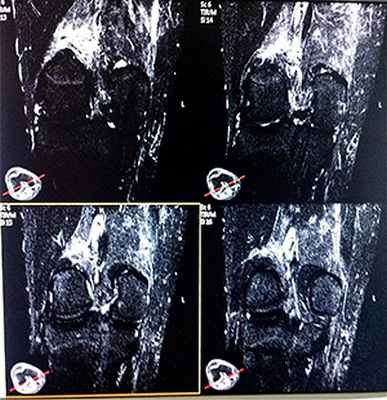

В полости правого коленного сустава определяется физиологическое количество жидкости. Небольшое количество выпота в области латерального бокового заворота.

Структура костной ткани существенно не изменена.

В области боковой поверхности медиального мыщелка бедренной кости и боковой поверхности латервльного мыщелка большеберцовой кости опредепяются небольшие очаги субхондрального фиброза костной ткани. В остальном структура костной ткани существенно не изменена.

Суставная щель не сужена со стороны внутренних мыщелков, конгруэнтность суставных поверхностей сохранена. Краевых остеофитов не выявлено. Сигнал хрящевого компонента сустава не снижен, суставной гиалиновый хрящ равномерный.

Структура заднего рога медиального мениска неоднородна за счет линейного, горизонтального включения повышенного МР-сигнала, не распространяющегося на суставные поверхности /II класс изменения МРС по Stoller/.

Передняя крестообразная связка имеет правильный ход волокон, не утолщена; задняя крестообразная связка без особенностей.

Целостность латерального мениска, коллатеральных связок сохранена. Собственная связка надколенникв без особенностей.

Клетчатка Гоффа незначительно фиброзирована.

Подколенная ямка не изменена.

Признаки повышения МР сигнала по Т2 ВИ и в режиме IR, снижения по Т1 от нижней трети /уровень визуализации/ медиальной широкой мышцы бедра. Аналогичные изменения определяются в периартикулярнои клетчатке.

Заключение: МР признаки повреждения медиальной широкой мышцы бедра. Небольшие дегенеративные изменения заднего рога медиального мениска. Явления бурсита.

При обнаружении патологии необходимо динамическое наблюдение.

Врач: Александров Е. В.